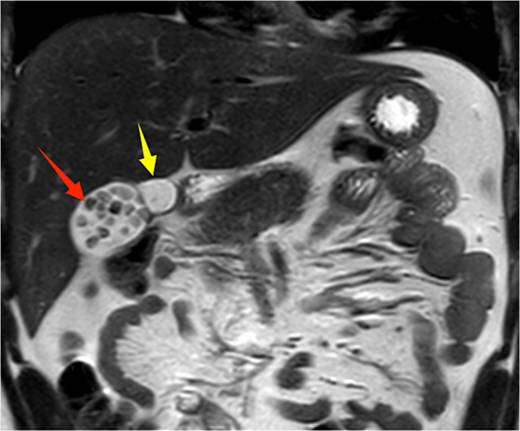

A 21-year-old male patient was admitted to our hospital with a 2-year history of intermittent right upper quadrant colicky pain. The symptoms initially occurred 2 years ago after consuming fried food, accompanied by nausea and vomiting, and were relieved after antispasmodic and analgesic treatment. Over the past 2 years, the symptoms recurred frequently, prompting the patient to seek further evaluation at our institution. The patient had no significant past medical history, including hypertension, diabetes, coronary heart disease, or other chronic conditions. He denied smoking, alcohol consumption, and any known drug allergies. Physical examination on admission revealed stable vital signs, with no jaundice observed in the skin or sclera. The abdomen was flat, with mild tenderness in the right upper quadrant and no rebound tenderness. The liver and spleen were not palpable. Murphy's sign was negative, abdominal percussion yielded tympanic sounds, and bowel sounds were normal. Laboratory tests, including complete blood count, liver function (bilirubin, ALT, AST, etc.), coagulation profile, amylase, lipase, and infection markers, were all within normal limits. Ultrasonography indicated multiple gallstones, a thickened and indistinct gallbladder wall, and suspicion of a folded gallbladder or possible double gallbladder malformation. To further delineate the biliary anatomy and ensure surgical safety, an abdominal MRI was performed. Magnetic resonance imaging (MRI) confirmed a double gallbladder malformation, with multiple stones in the lateral gallbladder (Figs 1 and 2). The clinical diagnosis was established as cholelithiasis with double gallbladder malformation.

Upper abdominal MRI demonstrates a double gallbladder variation. The two arrows indicate the respective gallbladders, the lateral one of which contains multiple gallstones.